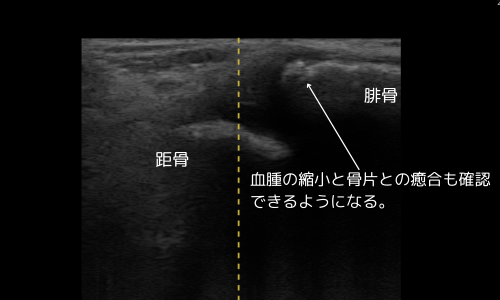

10月17日(受傷約3週間)

- 血腫縮小、骨片の癒合進行をエコーで確認

- 腫脹・圧痛ともに消失 → 医師より全荷重(FWB)許可、固定解除

- 軽量サポーター装着、ROM訓練開始